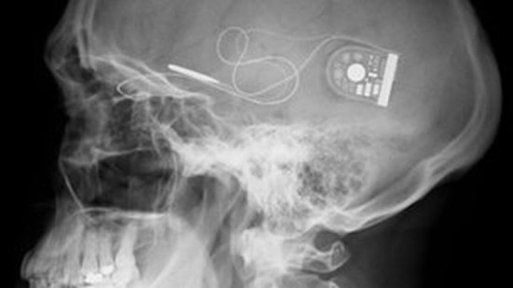

Dos pacientes totalmente ciegos, Chris James y Roben Millar, han conseguido recuperar parcialmente la visión gracias a la instalación detrás de sus retinas de un sensor fotográfico de 3mm con 1500 pixels de resolución.

Ambos pacientes, quienes perdieron la visión debido al transtorno ocular conocido como Retinitis Pigmentaria, recibieron estos implantes que recogen la luz y transmiten sus señales electrónicas al nervio óptico y, de allí, al cerebro. Las pruebas iniciales han permitido a los pacientes ver instantes de luz e incluso han podido identificar líneas rectas y curvas. La investigación se encuentra en su fase primaria, es necesario que el cerebo aprenda a interpretar las señales, sin embargo los resultados de esta prueba inicial abren un nuevo camino y hace que personas invidentes con ciertas patologías puedan albergar esperanzas de recuperar parte de su visión.